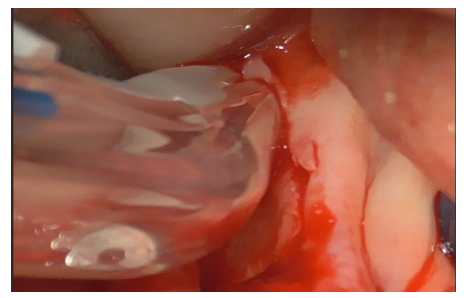

The peri-implantitis-affected implant was probed, revealing profuse bleeding (Figures 8-11).

Figure 8

Figure 9

Figure 10

Figure 11